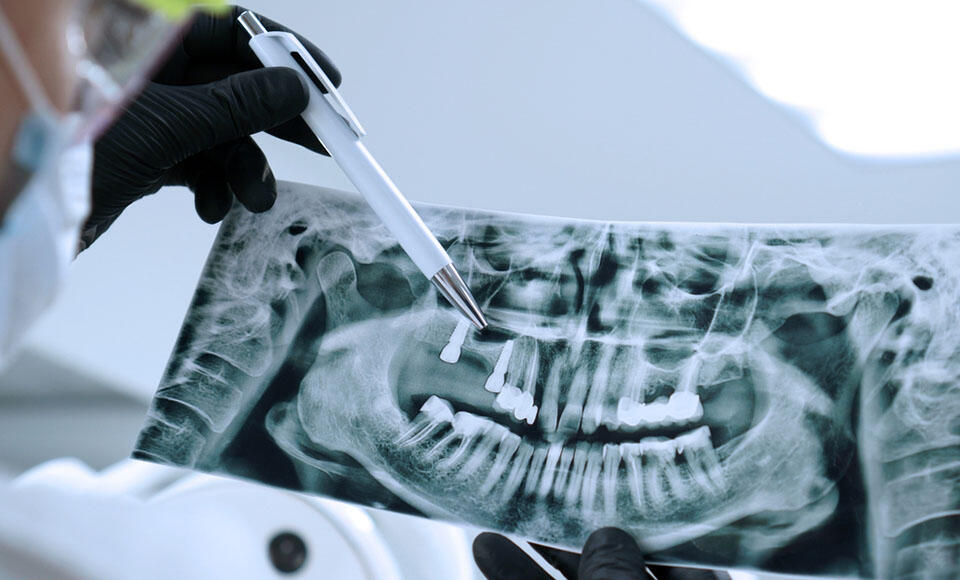

Cone Beam 3D: un insostituibile alleato per lo studio odontoiatrico

Le apparecchiature Cone Beam 3D (o Cone-Beam CT) si stanno diffondendo sempre di più negli studi odontoiatrici, portando notevoli benefici.

Ecco perché adottare lo scanner 3D è la scelta più giusta per il tuo Studio

In odontoiatria il versante tecnologico ricopre un’importanza sempre maggiore: le tecnologie 3D sono sempre più in grado di semplificare in maniera significativa la riabilitazione clinica di un paziente.